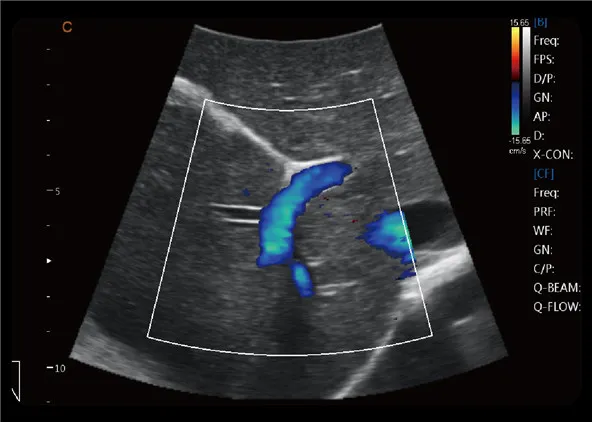

Zoom C HD

Haga zoom en la información de color, siga siendo la alta resolución.

Importante para la detección de información de sangre de vasos pequeños, especialmente para el diagnóstico de corazón fetal.